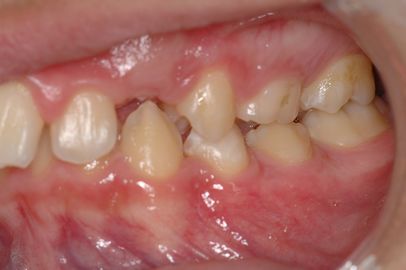

12-year-old patient who shows to the cephalometric examination, a underdevelopment of the jaw, which is small and not very projected, and imprisoned in the maxilla. The hypodivergent growth also determines a severe deep bite that does not allow the eruption of the upper canines in the presence of 2nd molar class. The trigeminal electrophysiological tests (not reported here) ensured that the patient, in the conditions in which he presented himself for the OrthoNeuroGnathodontic treatment, was in a State of System's integrity, such that the occlusal imperfection could be corrected through classic orthodontic masticatory rehabilitation. If the electrophysiological responses had shown neuromotor discrepancies, a State of system's destructurated would have been added to the occlusal imperfection to be treated with functional neuro-gnathological therapies to restore the state of System integrity (Figures 1, 2 and 3). The cephalometric analysis showed a skeletal Class 2 morphology, hypodivergent, biretrusive profile with SNA 80 °, SNB 75 ° and ANB 5 °.